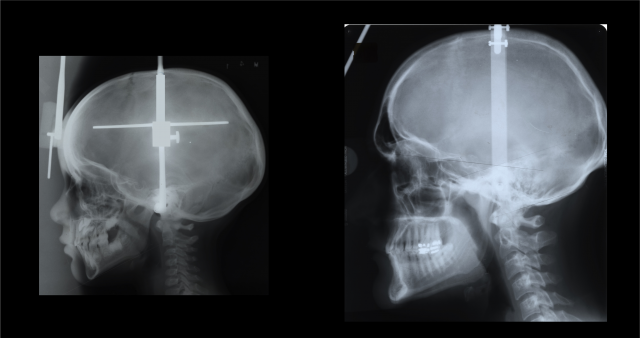

Desarrollamos la barbilla a medida que crecemos. A los 4 años (izquierda) y a los 20 (derecha). Fuente: UI.